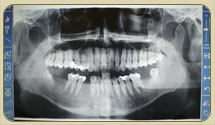

Digital Radiology

All x-ray images including all intra-oral radiographs & panoramics are in a digital format, viewed on a computer screen and thus requiring less than one third of the radiation doses as compared with a conventional X-ray film.